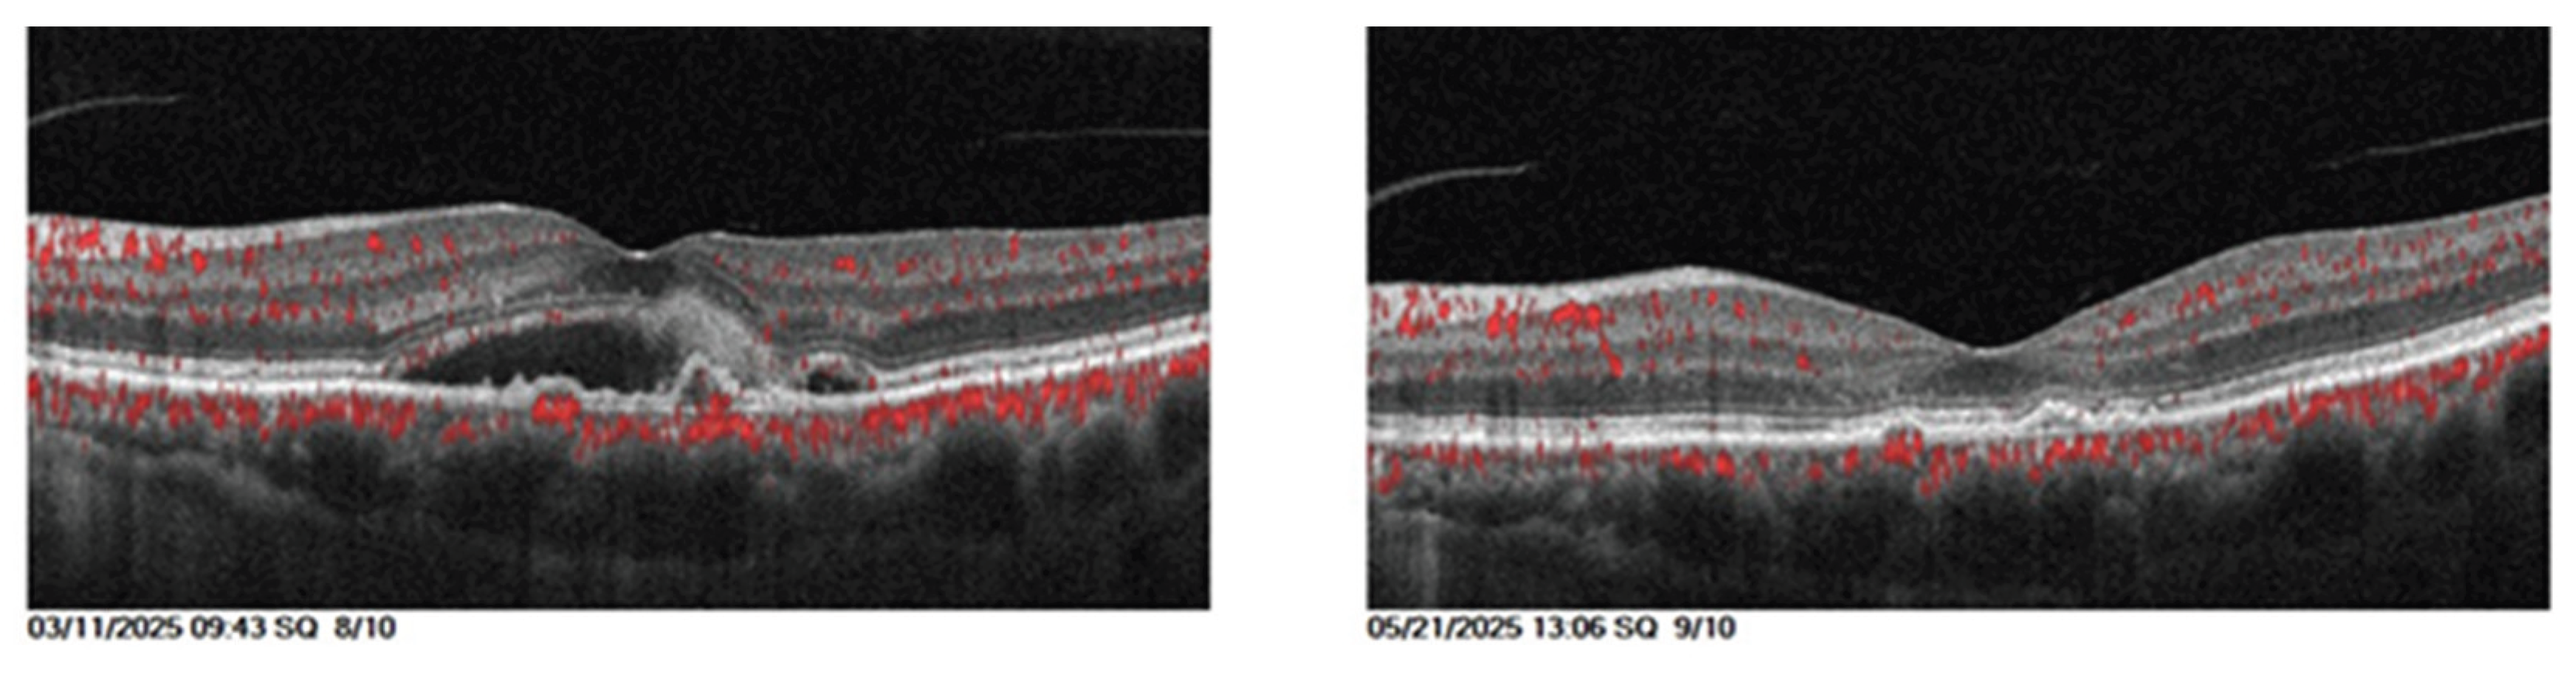

The comparison of clinical parameters before and after starting Faricimab was detailed in Table 5. Example on the anatomical outcome showed in Figure 5.

Visual acuity and central retinal thickness show a significant improvement (P<0.001). The mean visual acuity reduced from 0.60 (SD±0.24) to 0.44 (SD±0.24) and mean central retinal thickness reduced from 464.74 (SD±112.99) to 288.5 (SD±85.04), 1 month after the third faricimab injection.

Intraretinal fluid and subretinal fluid show significant reduction (P<0.001). The proportion of eyes with SRF decreased from 15 (32.60%) pretreatment to 2 (4.34%) posttreatment, while the proportion of eyes with IRF decreased from 46 (100%) to 19 (41.30%). Intraocular pressure remained stable over the course of the study (p=0.673).

Figure 5. 68-year-old female with diabetic macular edema with previous five intravitreal aflibercept injections with persistent CMO and IRF, and after three loading doses of Faricimab, the retina was dry, and visual acuity improved from 1 to 0.6.